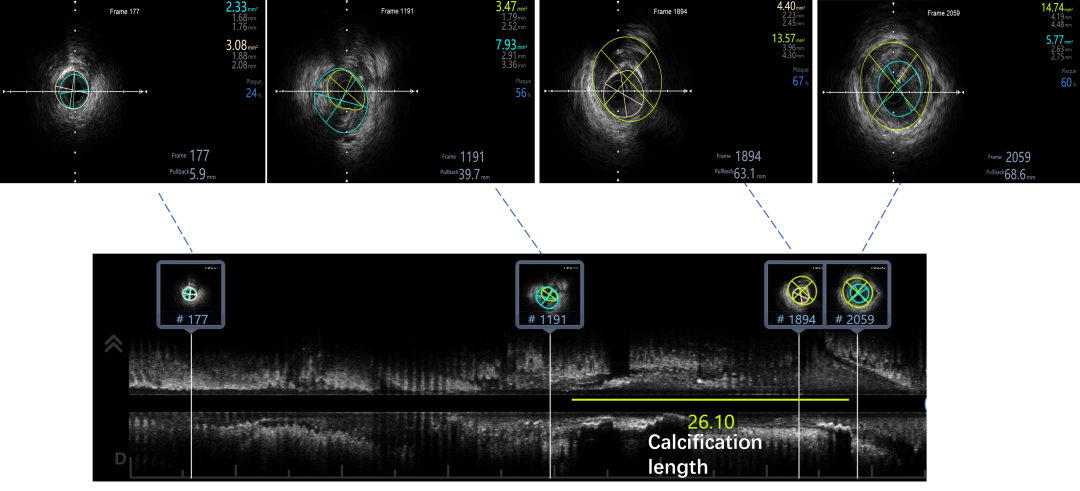

IVUS提示LAD近中段弥漫钙化,接近270度,钙化长度约26mm

LAD Stent 2.5*36mm,3.0*29mm ;Immediate image ,TIMI3